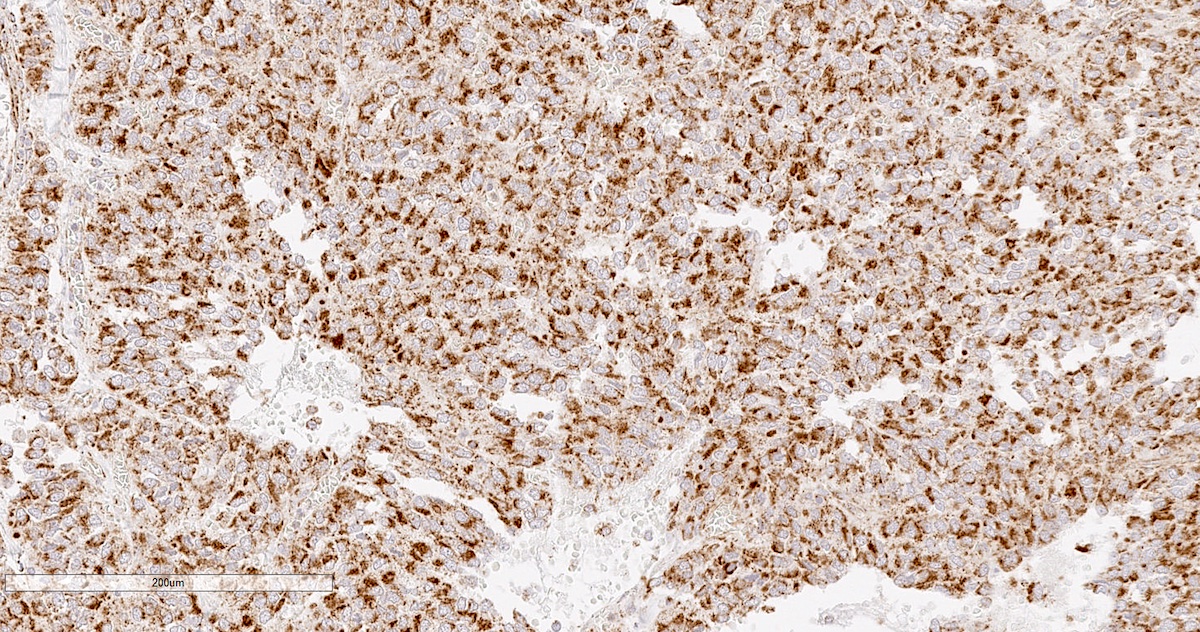

Microscopic (histologic) description

- Prevailing histologic pattern: epithelioid chief cells arranged in distinctive clusters / nests (zellballen pattern), separated by prominent fibrovascular stroma (J Clin Med 2018;7:280)

- Trabecular pattern: ribbons or cords of epithelioid cells divided by fibrous bands

- Other patterns: pseudorosette, angioma-like, spindled and sclerosing

- Chief cells: round, oval to polygonal cells with abundant granular basophilic, eosinophilic or amphophilic cytoplasm (Surg Pathol Clin 2019;12:951)

- Intracytoplasmic hyaline globules may be present in sympathoadrenal paragangliomas

- Giant multinucleated cells and bizarre cells can be present (Srp Arh Celok Lek 2002;130:7)

- Rarely, elongated and spindle shaped cells with a sarcomatoid appearance may be found

- Scattered ganglion cells can be seen

- May have nuclear atypia

- May have dysmorphic vessels, melanin-like pigment (neuromelanin) (pigmented paraganglioma), amyloid, abundant stroma and osseous metaplasia (Diagn Pathol 2012;7:77, Hum Pathol 1992;23:33)

- No or rare mitotic figures except in highly aggressive rapidly proliferating lesions

- May have focal chronic inflammatory infiltrate

- Necrosis is unusual except in patients who have undergone preoperative tumor embolization

- Special histopathologic features usually related to genetic syndromes:

- VHL syndrome: prominent stromal edema, clear cytoplasm and lipid degeneration (Am J Surg Pathol 1987;11:480)

- SDHx related syndrome: granular eosinophilic cytoplasm (Am J Surg Pathol 2020;44:422)

- MEN2 syndrome: unilateral or bilateral adrenal medullary hyperplasia (Neoplasia 2014;16:868)

Microscopic (histologic) images

Contributed by Luvy Delfin, M.D. and Sylvia L. Asa, M.D., Ph.D.